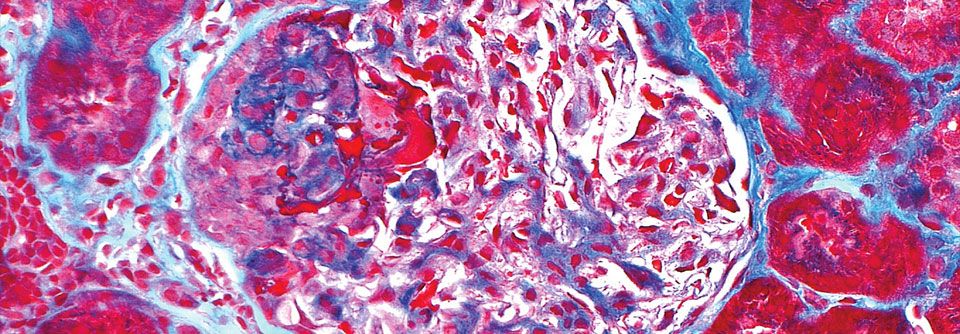

Glomerulonephritis bei ANCA-Vaskulitis im histologischen Schnitt. Zu sehen

ist ein Glomerulus mit typischer halbmondförmiger Schädigung (oben links). Glomerulonephritis bei ANCA-Vaskulitis im histologischen Schnitt. Zu sehen ist ein Glomerulus mit typischer halbmondförmiger Schädigung (oben links). © Science Photo Library / ZIAD M. EL-ZAATARI